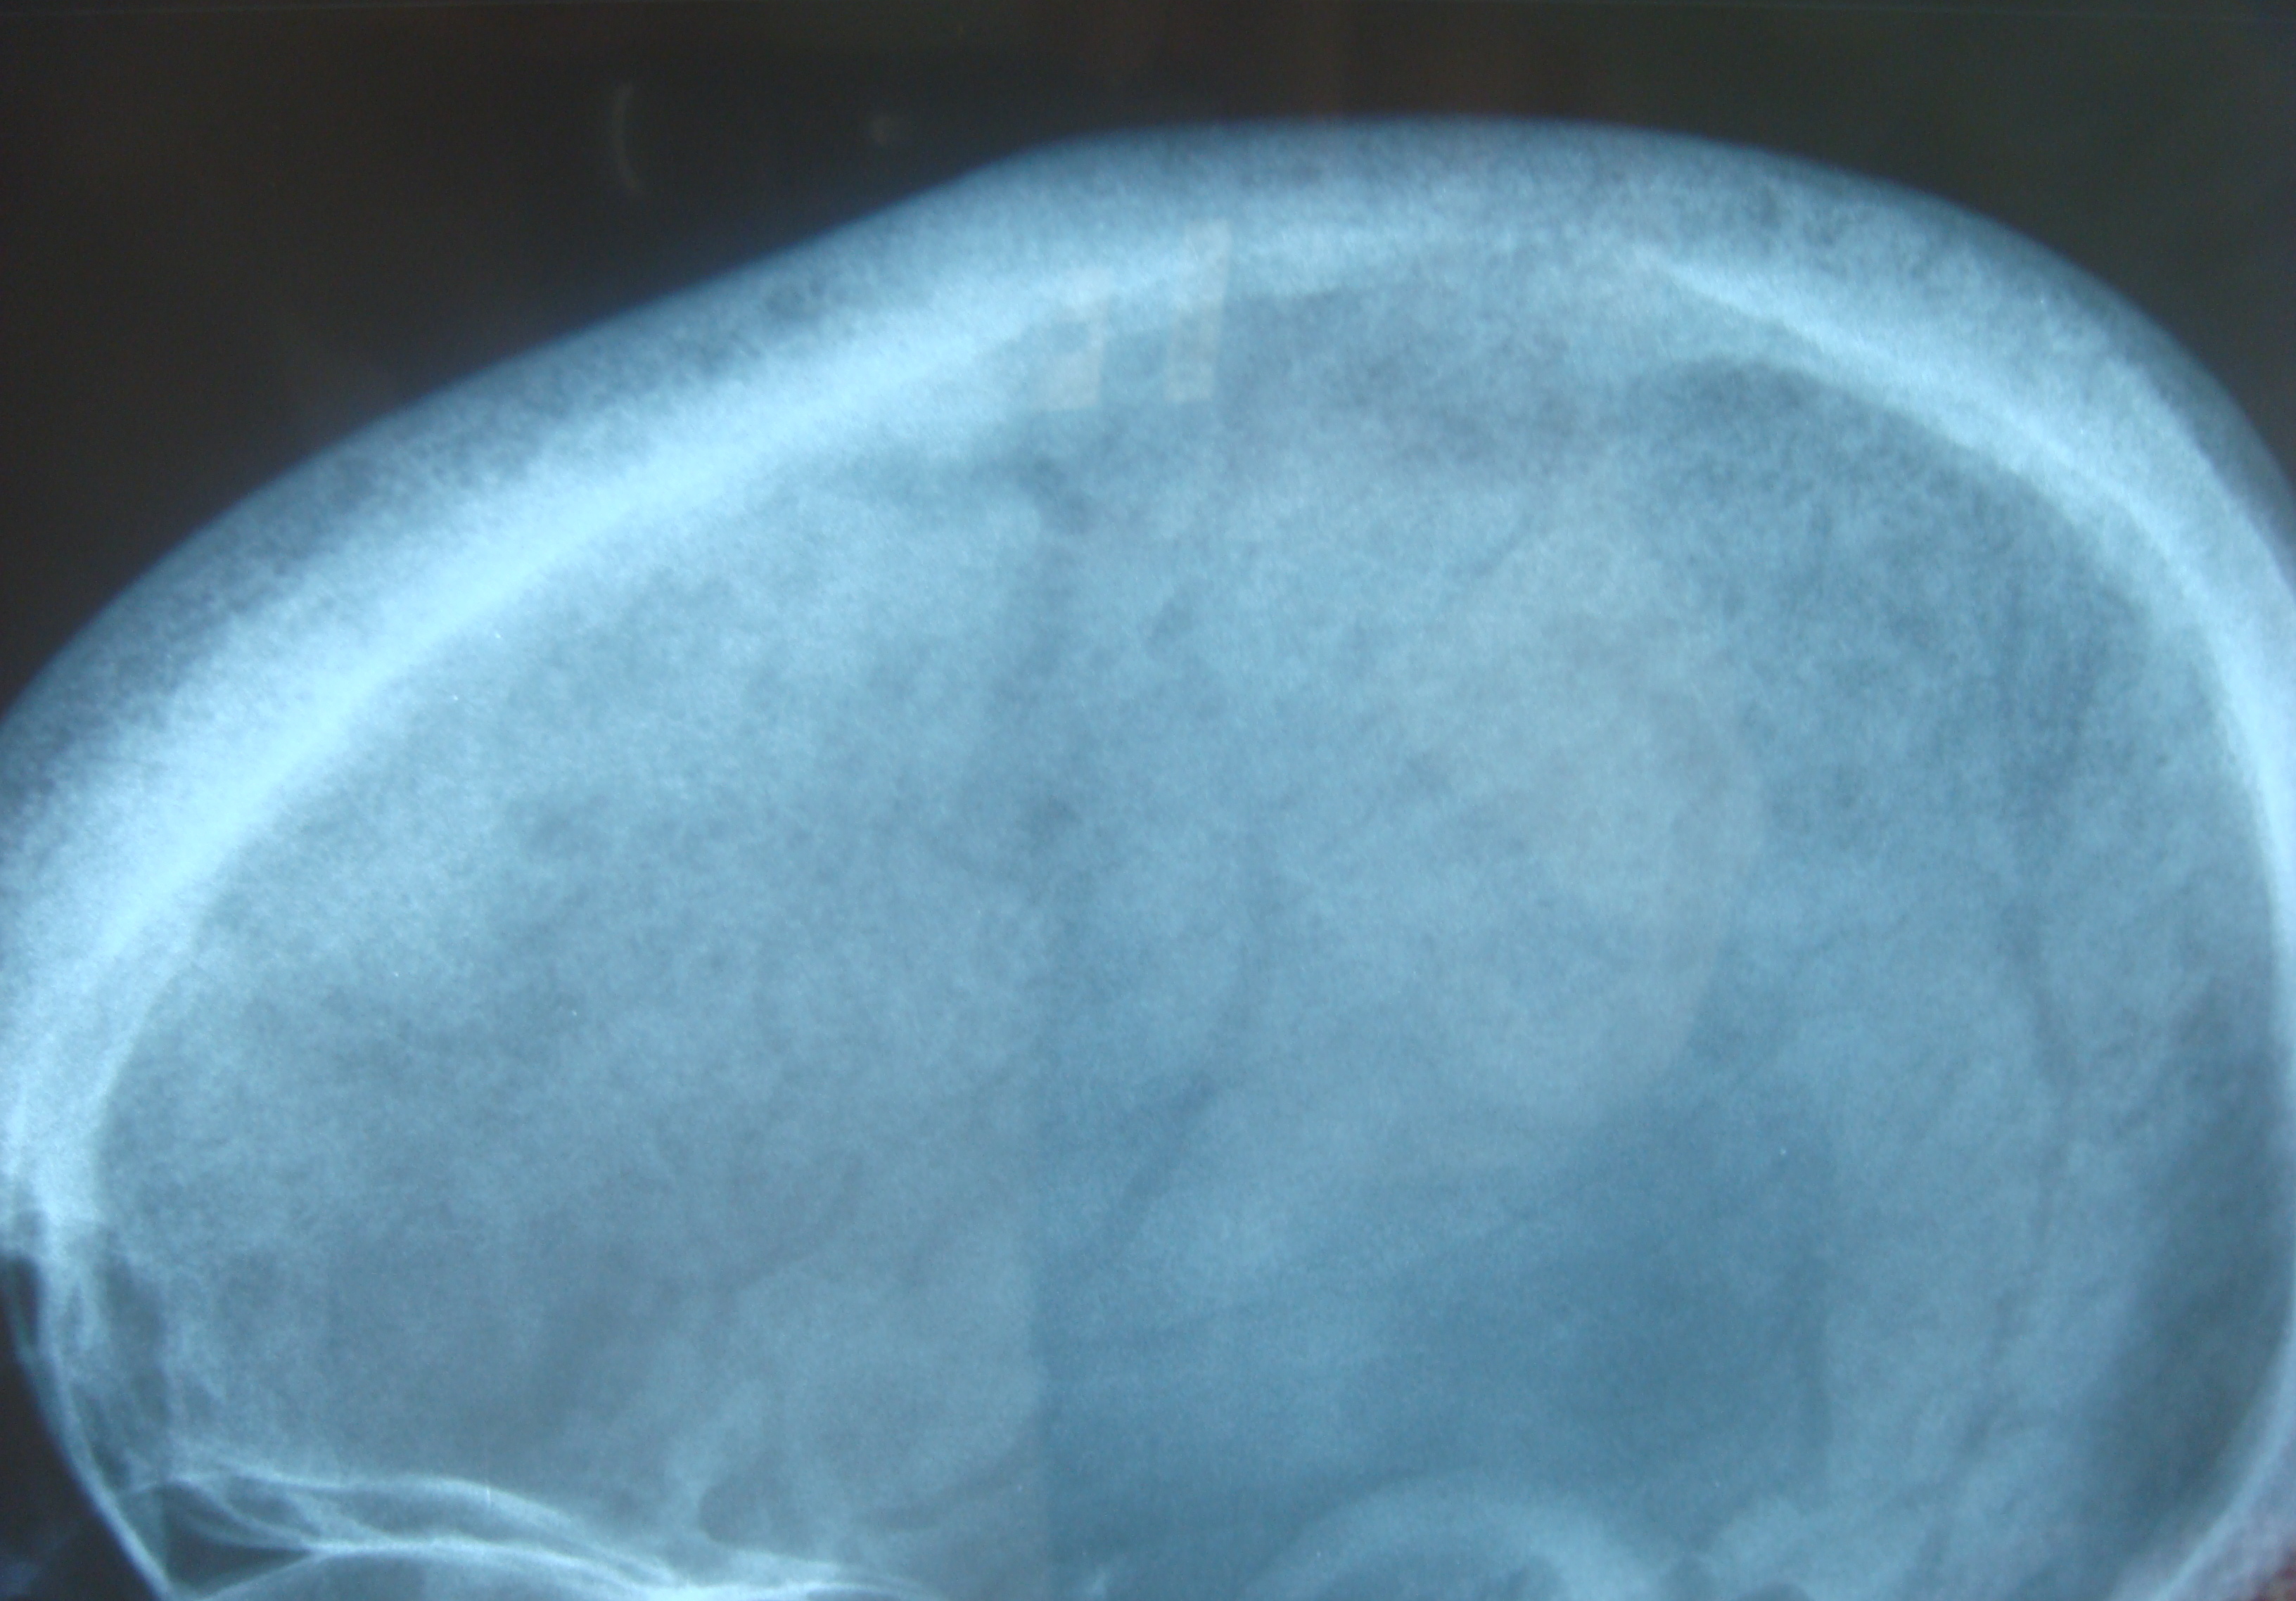

고칼슘혈증으로 인해 다양한 증상이 나타날 수 있는데, 흔한 증상으로는 변비, 구토, 권태감, 무기력증, 피로, 우울증, 뼈 통증(골통), 근육통, 관절통, 식욕 감퇴, 오심, 복통, 췌장염, 소변을 자주 보는 다뇨증, 심한 갈증, 인지 장애, 신결석, 현기증 등이 있다.[9][10] 또한 골밀도가 낮아지는 골감소증이나 골다공증이 발생할 수 있으며,[9][10] 방광결석이 생기기도 한다. 뼈 흡수가 진행되면 라켓 손톱(단지증)이 나타날 수 있고,[11] 방사선 사진에서는 럭비선수 척추라는 특징적인 소견이 관찰되기도 한다.[12] 신결석은 특히 흔한 초기 증상 중 하나인데, 이는 고칼슘혈증으로 인해 소변으로 배출되는 칼슘 양이 증가하고(고칼슘뇨증), 동시에 높은 PTH 수치로 인해 소변의 인산염 배설도 늘어나면서 칼슘과 인산염이 결합하여 결석을 형성하기 쉽기 때문이다.[7][8] 임상 검사에서 부갑상선 선종이 발견되는 경우는 매우 드물다.

고칼슘혈증 상태에서는 다른 혈액 검사 소견도 나타날 수 있다. 예를 들어, 고염소혈증이 동반되거나 신장에서 중탄산염의 손실이 증가하여 정상 음이온 차이를 보이는 대사성 산증이 발생할 수 있다.[60] 또한, 뼈의 교체율(turnover)이 증가하면서 알칼리성 인산가수분해효소(ALP) 수치가 상승할 수 있다. 원발성 고칼슘혈증의 경우, 혈청 칼슘 수치가 높음에도 불구하고 ALP 수치가 정상 범위 내에 있을 수 있지만, 이는 칼슘 수치를 고려했을 때 부적절하게 정상인 것으로 해석될 수 있다.